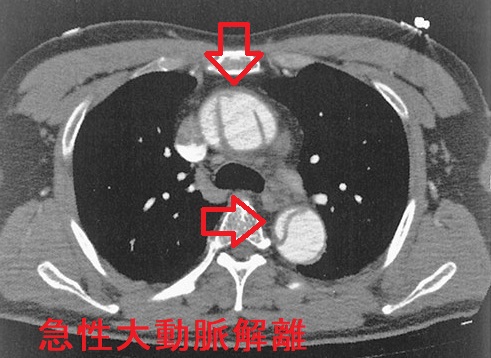

甲状腺機能低下症/潜在性甲状腺機能低下症/橋本病で動脈硬化が進行、急性大動脈解離とDIC・心タンポナーデ、腹部大動脈瘤、甲状腺動脈瘤破裂おこる。急性大動脈解離は血中Dダイマー上昇。A型上行大動脈解離が大動脈基部に及ぶと心臓栄養する冠状動脈入口部を圧迫、急性心筋梗塞と同じ心電図所見に。B型解離(DeBakey III)で主要分枝を含まない領域に限局は降圧治療のみ。甲状腺動脈瘤は血栓塞栓症なく、高率に破裂し死亡率20%のため無症候性でもコイル塞栓術、外科的切除。動脈硬化進行してできる腹部大動脈瘤は破裂すると突然死。通常、無症状で破裂始まると腹痛・腰痛。

急性大動脈解離とは、大動脈壁の脆弱さ、動脈硬化、高血圧などが原因で、血管内膜に亀裂が入り、中膜が裂け、内腔側が内膜フラップ(intimal flap)になって、その下に偽腔が生じる病態です。

急性大動脈解離の症状は、前胸部から裂けた箇所[喉(のど)、背中、腰部など]に広がる突然の激しい胸痛、背部痛(70~80%)。9~20%は無痛性。「喉(のど)の痛み」が主症状(主訴)で軽い胸痛、背部痛だと、耳鼻咽喉科・内科・甲状腺専門医を受診して急性大動脈解離の診断が遅れる場合があります。当然、甲状腺にも喉(のど)にも痛みの原因は無く、逆流性食道炎・非びらん性胃食道逆流(NERD)、狭心症の放散痛の除外診断目的で消化器内科、循環器内科を受診することになりますが、循環器内科を速やかに受診すれば急性大動脈解離を見つけられるかもしれません。

急性大動脈解離では肺血栓塞栓症(肺梗塞)同様、血中Dダイマーが上昇します。